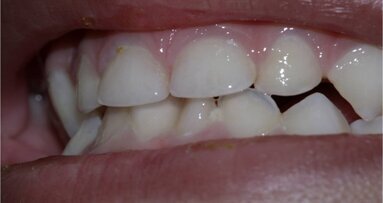

The dental structure most affected by radiotherapy is dentine, owing to its high organic content. Some of the alterations are caused by a process called radiolysis, leading to dehydration of the substrate, breakdown of the odontoblastic extensions and collagen fibrils, and cracks and fissures around the dentinal tubules. These alterations make the dental structure more susceptible to fracture and increase the dentinal roughness, which in turn affects the interaction between the substrate and microorganisms. Therefore, microbial colonisation, followed by the establishment of a more complex and structured biofilm, may occur. Bearing this in mind, endodontists need to redirect their treatment procedures regarding patients who have undergone radiotherapy in order to achieve endodontic success and restore oral health.